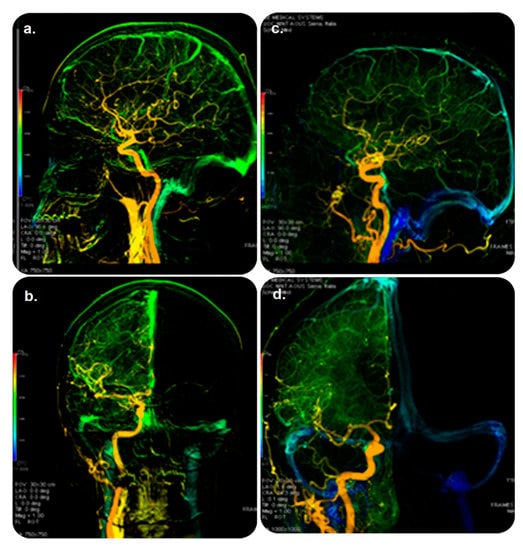

This software uses multicolored DSA to produce sequenced parametric images of peak opacification simultaneously with peak times to allow users to visualize vascular-flow-related features. It examines a single image and summarizes the major data contained in a DSA time series to recognize vascular flow. Furthermore, AngioViz automatically synchronizes various DSA series for flow comparison and can interpret a complex flow model of several anatomical regions. AngioViz can be used with AW VolumeShare 5 and higher [19]. Our search revealed no evidence of its practical clinical impact (Figure 3).

Figure 3. AngioViz software and its role in guiding therapy. DSA examination: (top) lateral and (bottom) anterior–posterior views of color-coded right carotid artery in controls (a,b) and patients (c,d) with multiple sclerosis. Blue color shown only in patients demonstrates prolonged cerebral circulation time. Veins are in green (and not in blue) in the controls (a,b). Abbreviations: DSA, digital subtraction angiography. Reprinted from “Cerebral circulation time is prolonged and not correlated with EDSS in multiple sclerosis patients: A study using digital subtracted angiography” by Monti et al. [20] with approval from the corresponding author and publisher (PLOS ONE; Copyright 2015 [open access license]).